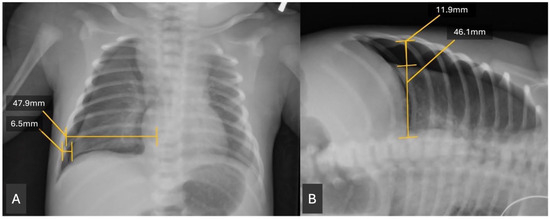

A retrospective chart review was conducted of the patients identified from the EMR query. Clinical data were extracted. Birth weight was obtained from the chart as the recorded birth weight in grams. Gestational age was calculated by recorded gestational age at birth, based on best obstetrical dating. In the absence of obstetrical dating, our routine practice is to perform a Ballard exam. Radiographs were reviewed using the Picture Archiving and Communication System (PACS). The size of the pneumothorax was assessed by measuring the widest transverse diameter of the pneumothorax on anteroposterior (AP) and, when available, lateral decubitus (DECUB) chest radiographs. This measurement was then divided by the widest transverse diameter of the hemithorax above the diaphragm to obtain a ratio (Figure 1). This measurement was modeled after similar measurements of pneumothorax radiographs in Ozer et al. 2013 [11]. A single investigator performed all radiographic measurements, so inter-rater reliability statistics were not assessed. The investigator was blinded to outcome.

Figure 1. (A,B): Example of pneumothorax (PTX) measurements. Transverse lines at the widest part of the PTX and the widest part of that hemidiaphragm are drawn and measured on both an AP film (left panel) and similarly on a lateral decubitus film if available (right panel). A simple ratio is created of the PTX/hemidiaphragm measurements. For A, ratio is calculated as follows: 6.5/47.9 = 0.136. For B, ratio is calculated as follows: 11.9/46.1 = 0.258.